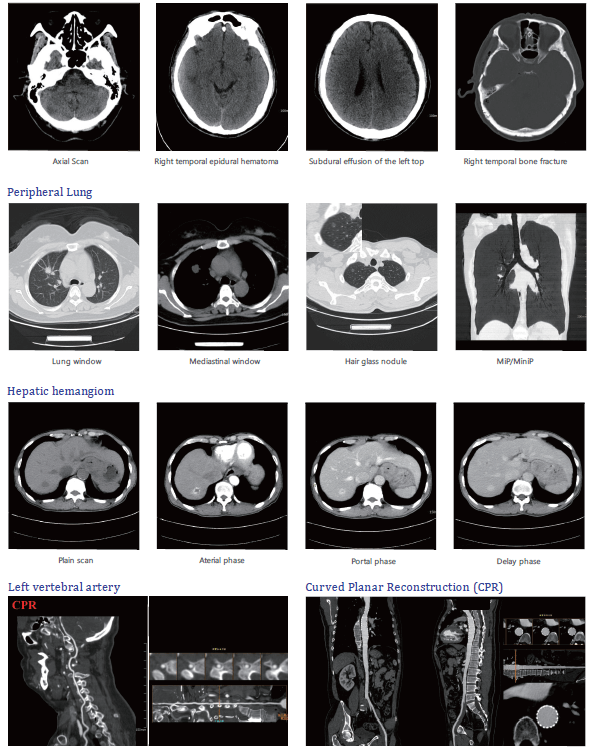

Clinical Gallery